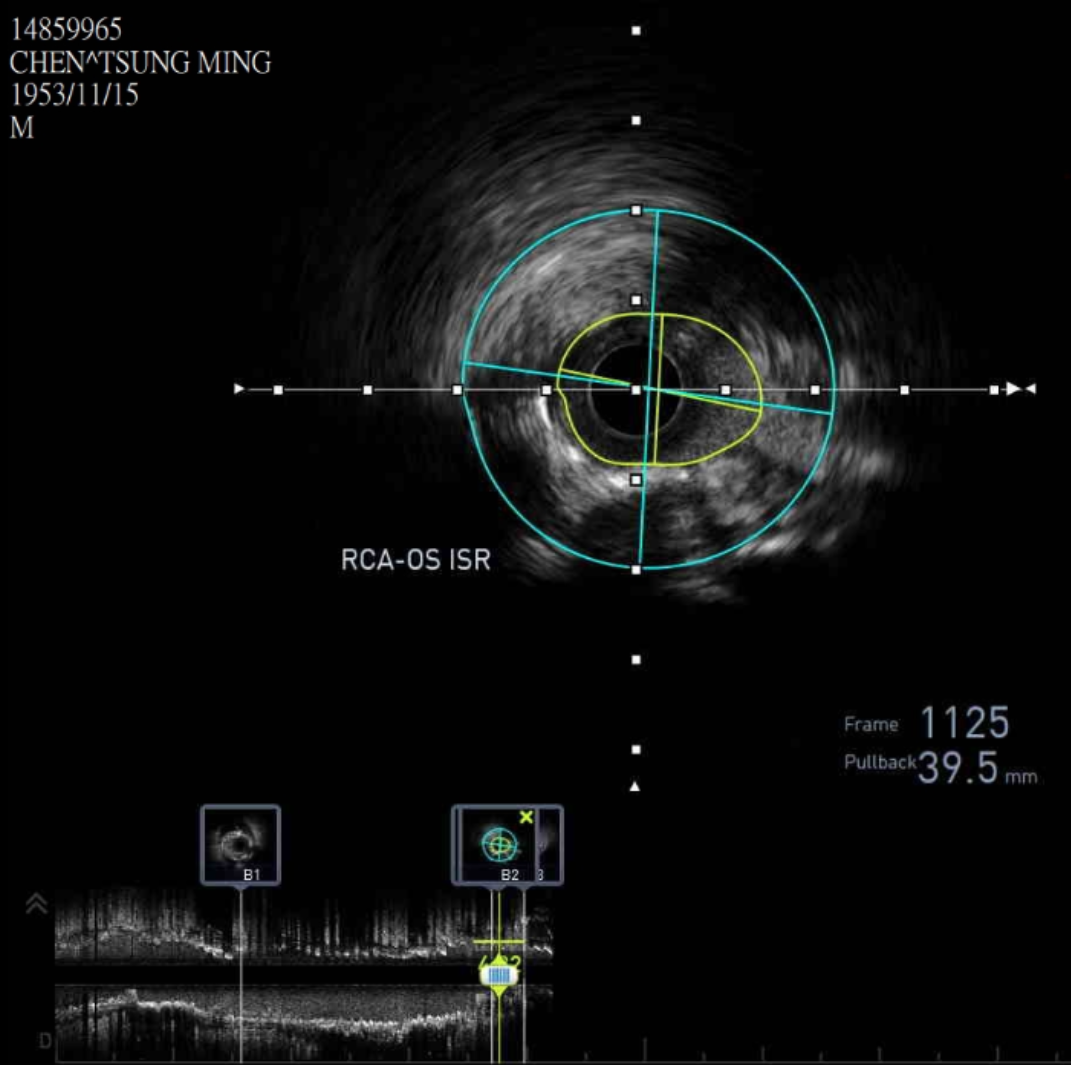

We advanced a 6F JR 4.0 SH 100cm guiding catheter and crossed the RCA ostial lesion using a Fielder FC guidewire. Pre-dilatation was performed with Ryurei 1.5¡¿15mm balloon. IVUS was then performed, revealing a patent stent in the proximal to mid RCA. However, the ostial RCA stent was under-expanded, with smooth muscle compressing the stent from outside. Balloon pre-dilatation was carried out using an NC Euphora 4.0¡¿12mm balloon, inflated up to 22 bar. However, the lesion was resistant and could not be fully dilated. We then applied a 4.0mm intravascular lithotripsy balloon with a total of 100 shocks delivered. But the effect was still minimal. The IVUS showed limited additional plaque fracture or vessel expansion. We tried NC Sapphire II 4.5¡¿8 mm balloon inflation to 18 bar, but it was ineffective due to balloon slippage. The angiogram after oversized NC dilation showed residual stenosis of 59%. We then selected a Wolverine Cutting Balloon 4.0¡¿10 mm and initiated dilation to 6 bar, which resulted in easy slippage again. Subsequent oversized dilations were performed at 18 bar, after which the lesion was successfully dilated. Using a Runthrough Floppy guidewire with the floating wire technique, a drug-eluting stent Biofreedom Ultra 4.0¡¿14 mm was deployed in the ostial RCA ISR. We inflated at 14 bar for 14 seconds, repeated twice. Final post-dilatation was performed with an Accuforce 4.0¡¿15mm balloon. The final IVUS showed good stent placement and expansion. We closed the procedure.

Case Summary